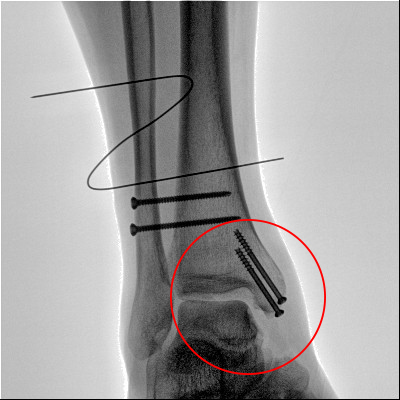

踝關(guān)節(jié)骨折在X影像上的表現(xiàn)有很多種。如內(nèi)踝骨折和外踝骨折,我們可以在影像上看到骨折處的骨折線是不連續(xù)的。還有后踝的骨折,內(nèi)踝、外踝、后踝聯(lián)合在一起發(fā)生的骨折,我們稱之為“三踝骨折”,這些都是在X影像上能夠顯示出來的。

內(nèi)踝骨折

外踝骨折